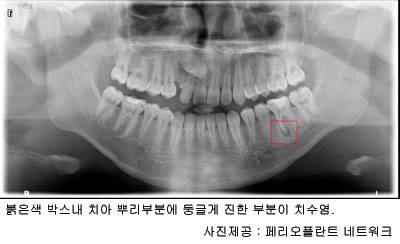

따라서 정상적인 치아는 치수가 외부와 차단돼 있지만, 충치가 생겨 치관부가 손상을 입어 치수가 외부에 노출되거나 혹은 혈액 속에 있는 세균감염으로 염증이 생길 수 있는데 이를 치수염이라고 한다. 치수염이 생기면 갑작스럽고 심한 통증이 특징이다. 급성치수염은 통증으로 인해 밤에 잠을 이루지 못할 정도다.

치수염의 가장 큰 원인이 되는 것은 충치다. 치아의 썩은 부위가 더욱 안으로 파고 들어가 치수 조직까지 박테리아가 침범해 치수염이 발생하게 되는데, 이를 방치하게 되면 치아의 뿌리 끝까지 확산돼 치근단(치근끝) 부위의 염증의 원인이 되고 치아를 싸고 있는 뼈까지 염증이 확산돼 치근단 질환을 유발하며 골수염과 같은 합병증을 일으킬 수 있고 심한 경우 턱뼈를 제거하는 수술을 받는 경우도 생길 수 있다.